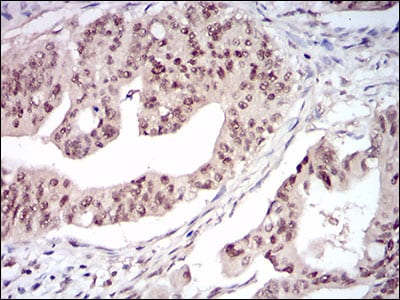

- Immunohistochemical analysis of paraffin-embedded human rectum cancer tissues using DNMT1 mouse mAb with DAB staining.